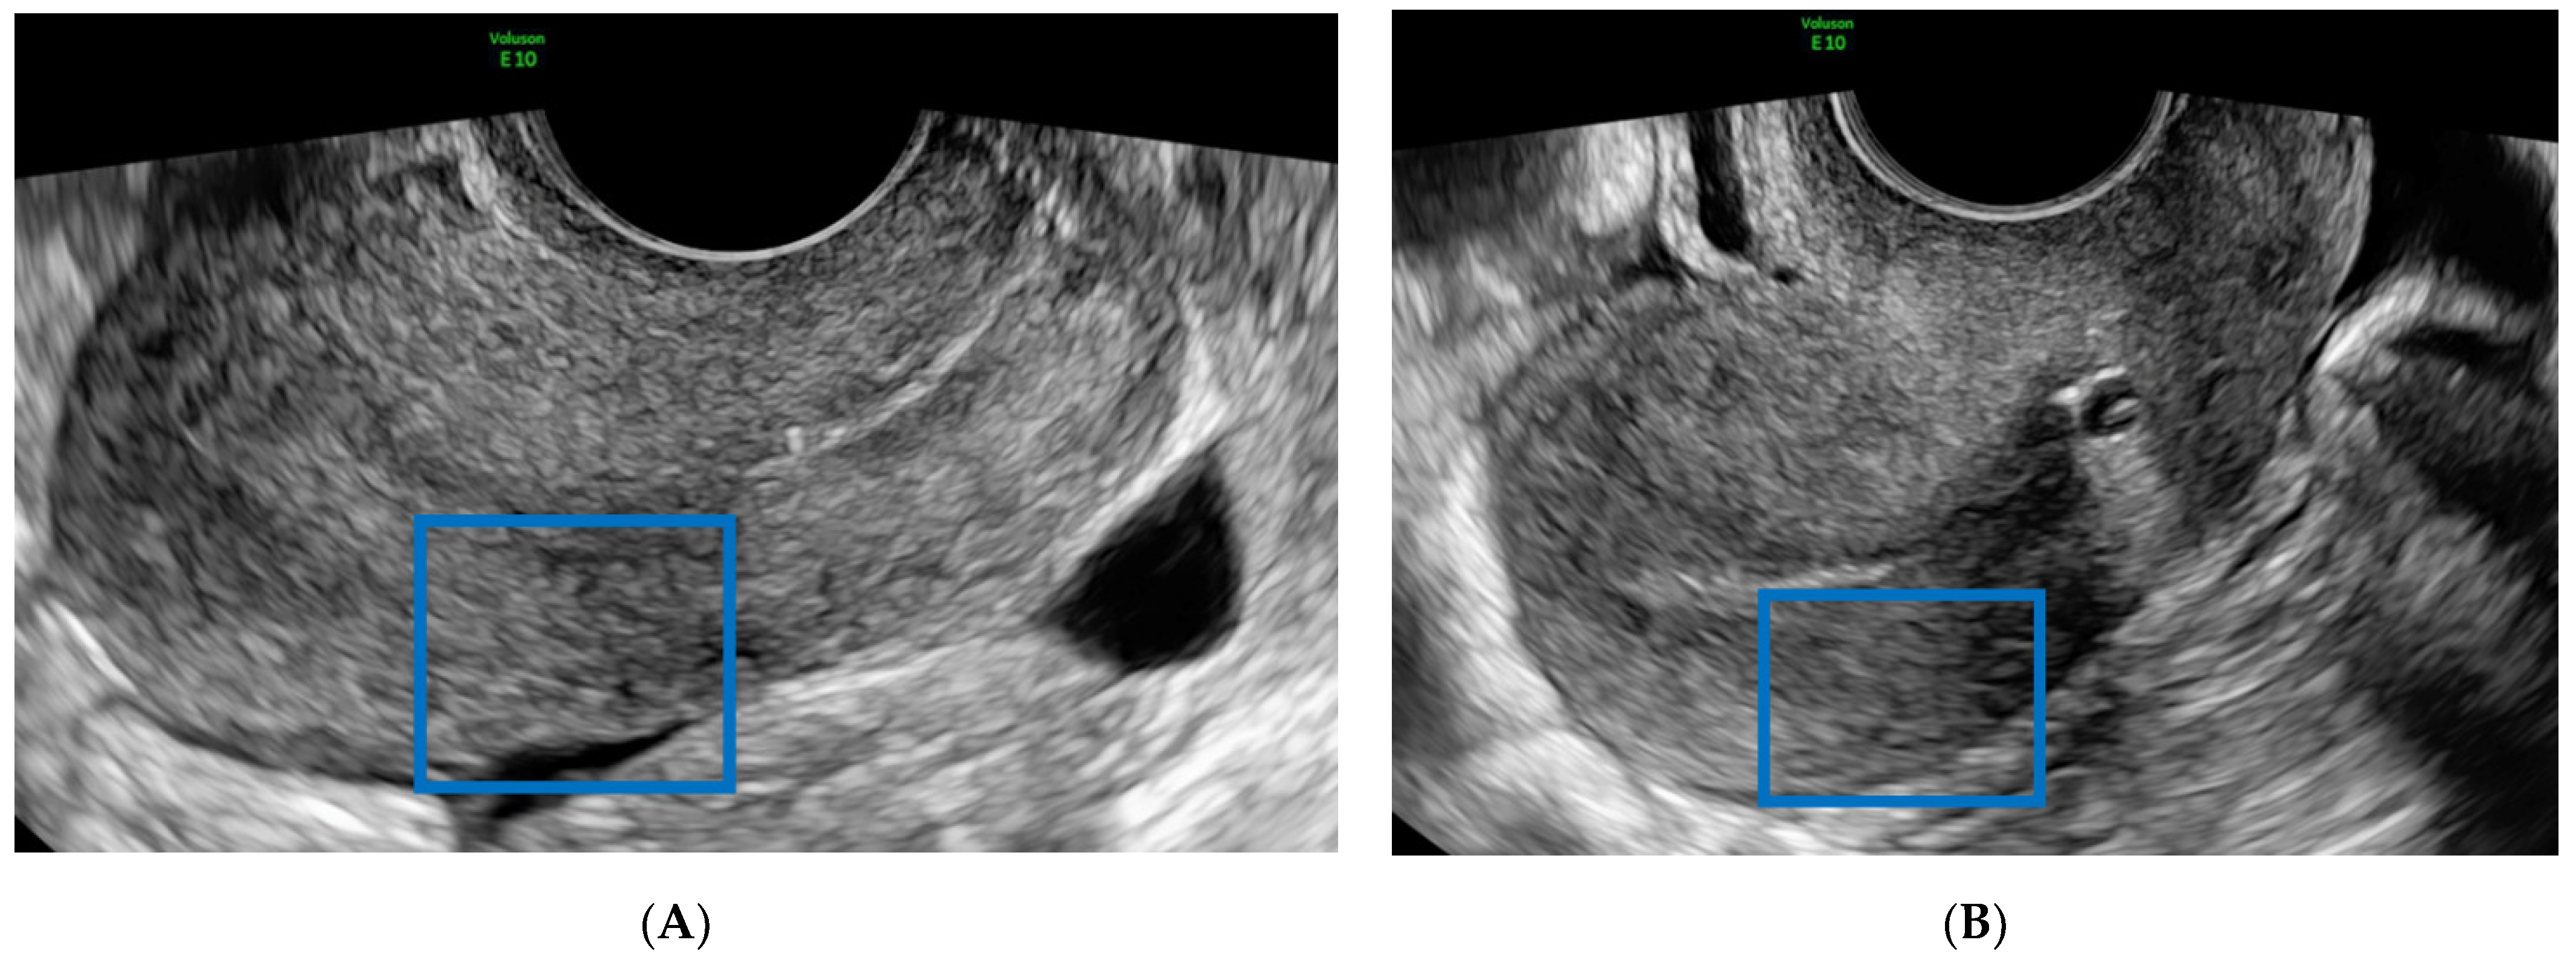

2. Case Report

- The presence of a hypoechoic, presumably endometriotic, nodule of approximately 2 cm in the fixed vesicouterine plica;

- Asymmetric myometrium and some minimal focal vacuolar areas in the anterior part of the uterine corpus, suggesting diffuse adenomyosis;

- A unilocular avascular ground glass cyst of (49 × 36 × 56) mm suggestive of a typical endometrioma in the left ovary;

- Both right and left uterosacral ligaments were thickened without lesions evident at the US.